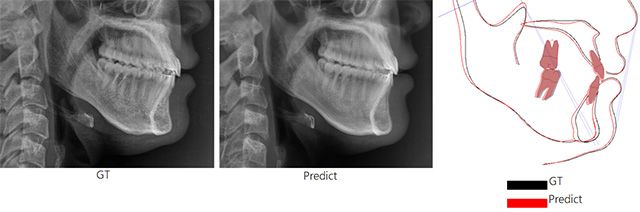

연구팀은 약 3만 장의 방사선 영상과 707명의 양악수술 환자 데이터를 기반으로 수술 전 환자의 해부학적 구조 데이터를 분석한 뒤, 그래프 신경망(Graph Neural Networks)과 확산모델(Diffusion Model)을 결합해 수술 후 모습을 예측한 측면 두부 방사선 영상을 생성하는 AI 모델을 개발했다.

연구팀은 AI 모델의 정확도 검증을 위해 교정과 전문의 2명과 구강악안면외과 전문의 2명이 AI 예측 영상과 실제 영상을 구분하는 테스트를 진행했다. 그 결과 전문의가 예측 영상과 실제 영상을 구분한 정확도는 48%로, 두 영상을 거의 구별하지 못했다. 실제 예측 영상과 실제 촬영 영상의 계측점 간 평균 오차는 대부분 1.5mm 이하였다.